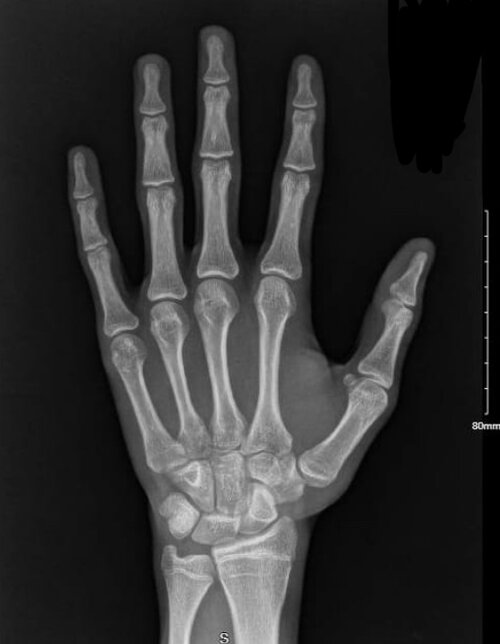

What is my bone age? (Xrays shown)

My doctor said its 17 years which means its 14 months older than my chronological age but i want a second opinion from some autist on this forum. Only reply if yk what ur talking abt. Im assuming its 90-95% closed but i hope my planned stack delays its closure

almost closed, over. maybe 16

it looks almost fully closed, i can see open plates in your thumb and miniscule amounts in the pinky

maybe you could gain 1-3cm at best